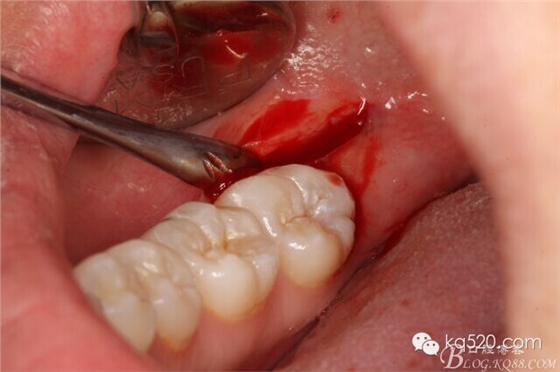

圖4.局部無痛麻醉注射

圖5.偏頰側、做直線微切口,切口約1cm。

圖6.翻小瓣

圖7.暴露48合面